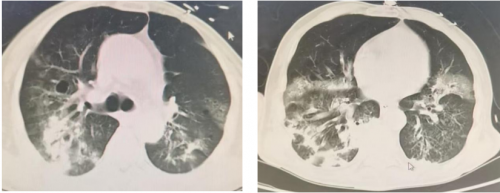

2025-10-22胸部CT:气管插管术后,气管腔内可见高密度影附着。桶状胸廓,双肺可见多发类圆形无壁及薄壁透光区,双肺内可见散在斑片状稍高密度影,边缘模糊不清,部分实变。双侧胸腔内可见弧形液体密度影。主动脉及冠状动脉走行区可见致密影。双侧胸腔内未见积液。

2025-10-28复查胸部CT:气管插管术后,气管腔内可见高密度影附着。桶状胸廓,双肺可见多发类圆形无壁及薄壁透光区,双肺内可见散在斑片状稍高密度影,边缘模糊不清,部分实变。双侧胸腔内可见弧形液体密度影,右侧为著。主动脉及冠状动脉走行区可见致密影。双侧胸腔内未见积液。